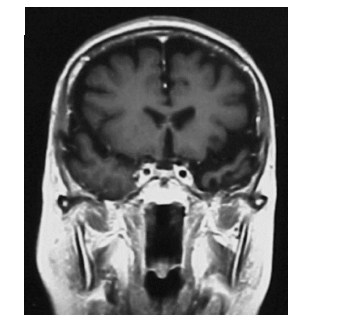

Observe abaixo a imagem por ressonância magnética

A imagem de um corte frontal mostra um paciente com demência semântica, em que se observa